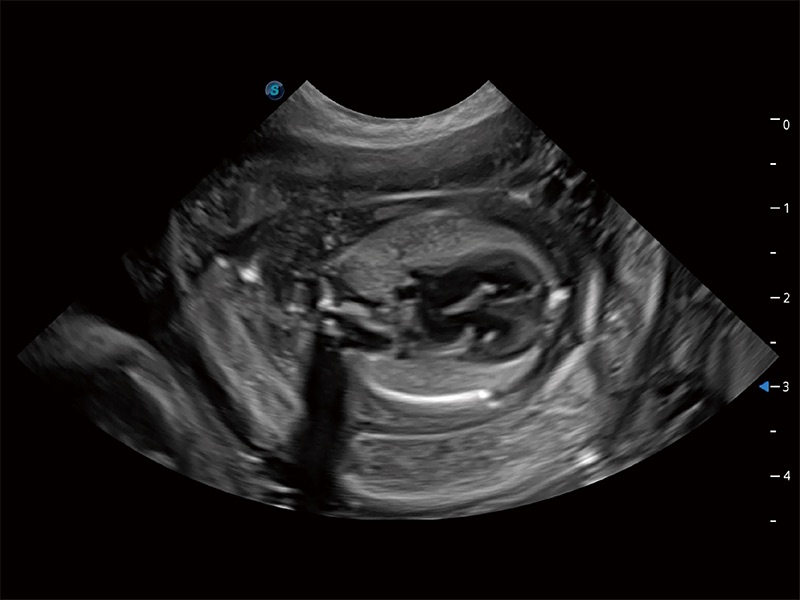

ProPet 80 配备了丰富的心脏探头群、先进的成像技术和专业的心脏测量工具,可帮助动物医生为不同体型和生理结构的动物提供心脏和心肌功能的全面评估。

ProPet 80 专为动物医生设计,对不同的动物体型和生理结构作出了针对性的优化。通过动物影像专用软件,可满足个性化的应用需求,帮助动物医生获得更精确的诊断数据。

为精细结构及组织边缘提供高清晰度的图像和更大的成像视野。帮助减轻医生的用眼疲劳,快速精准获得测量的数据。